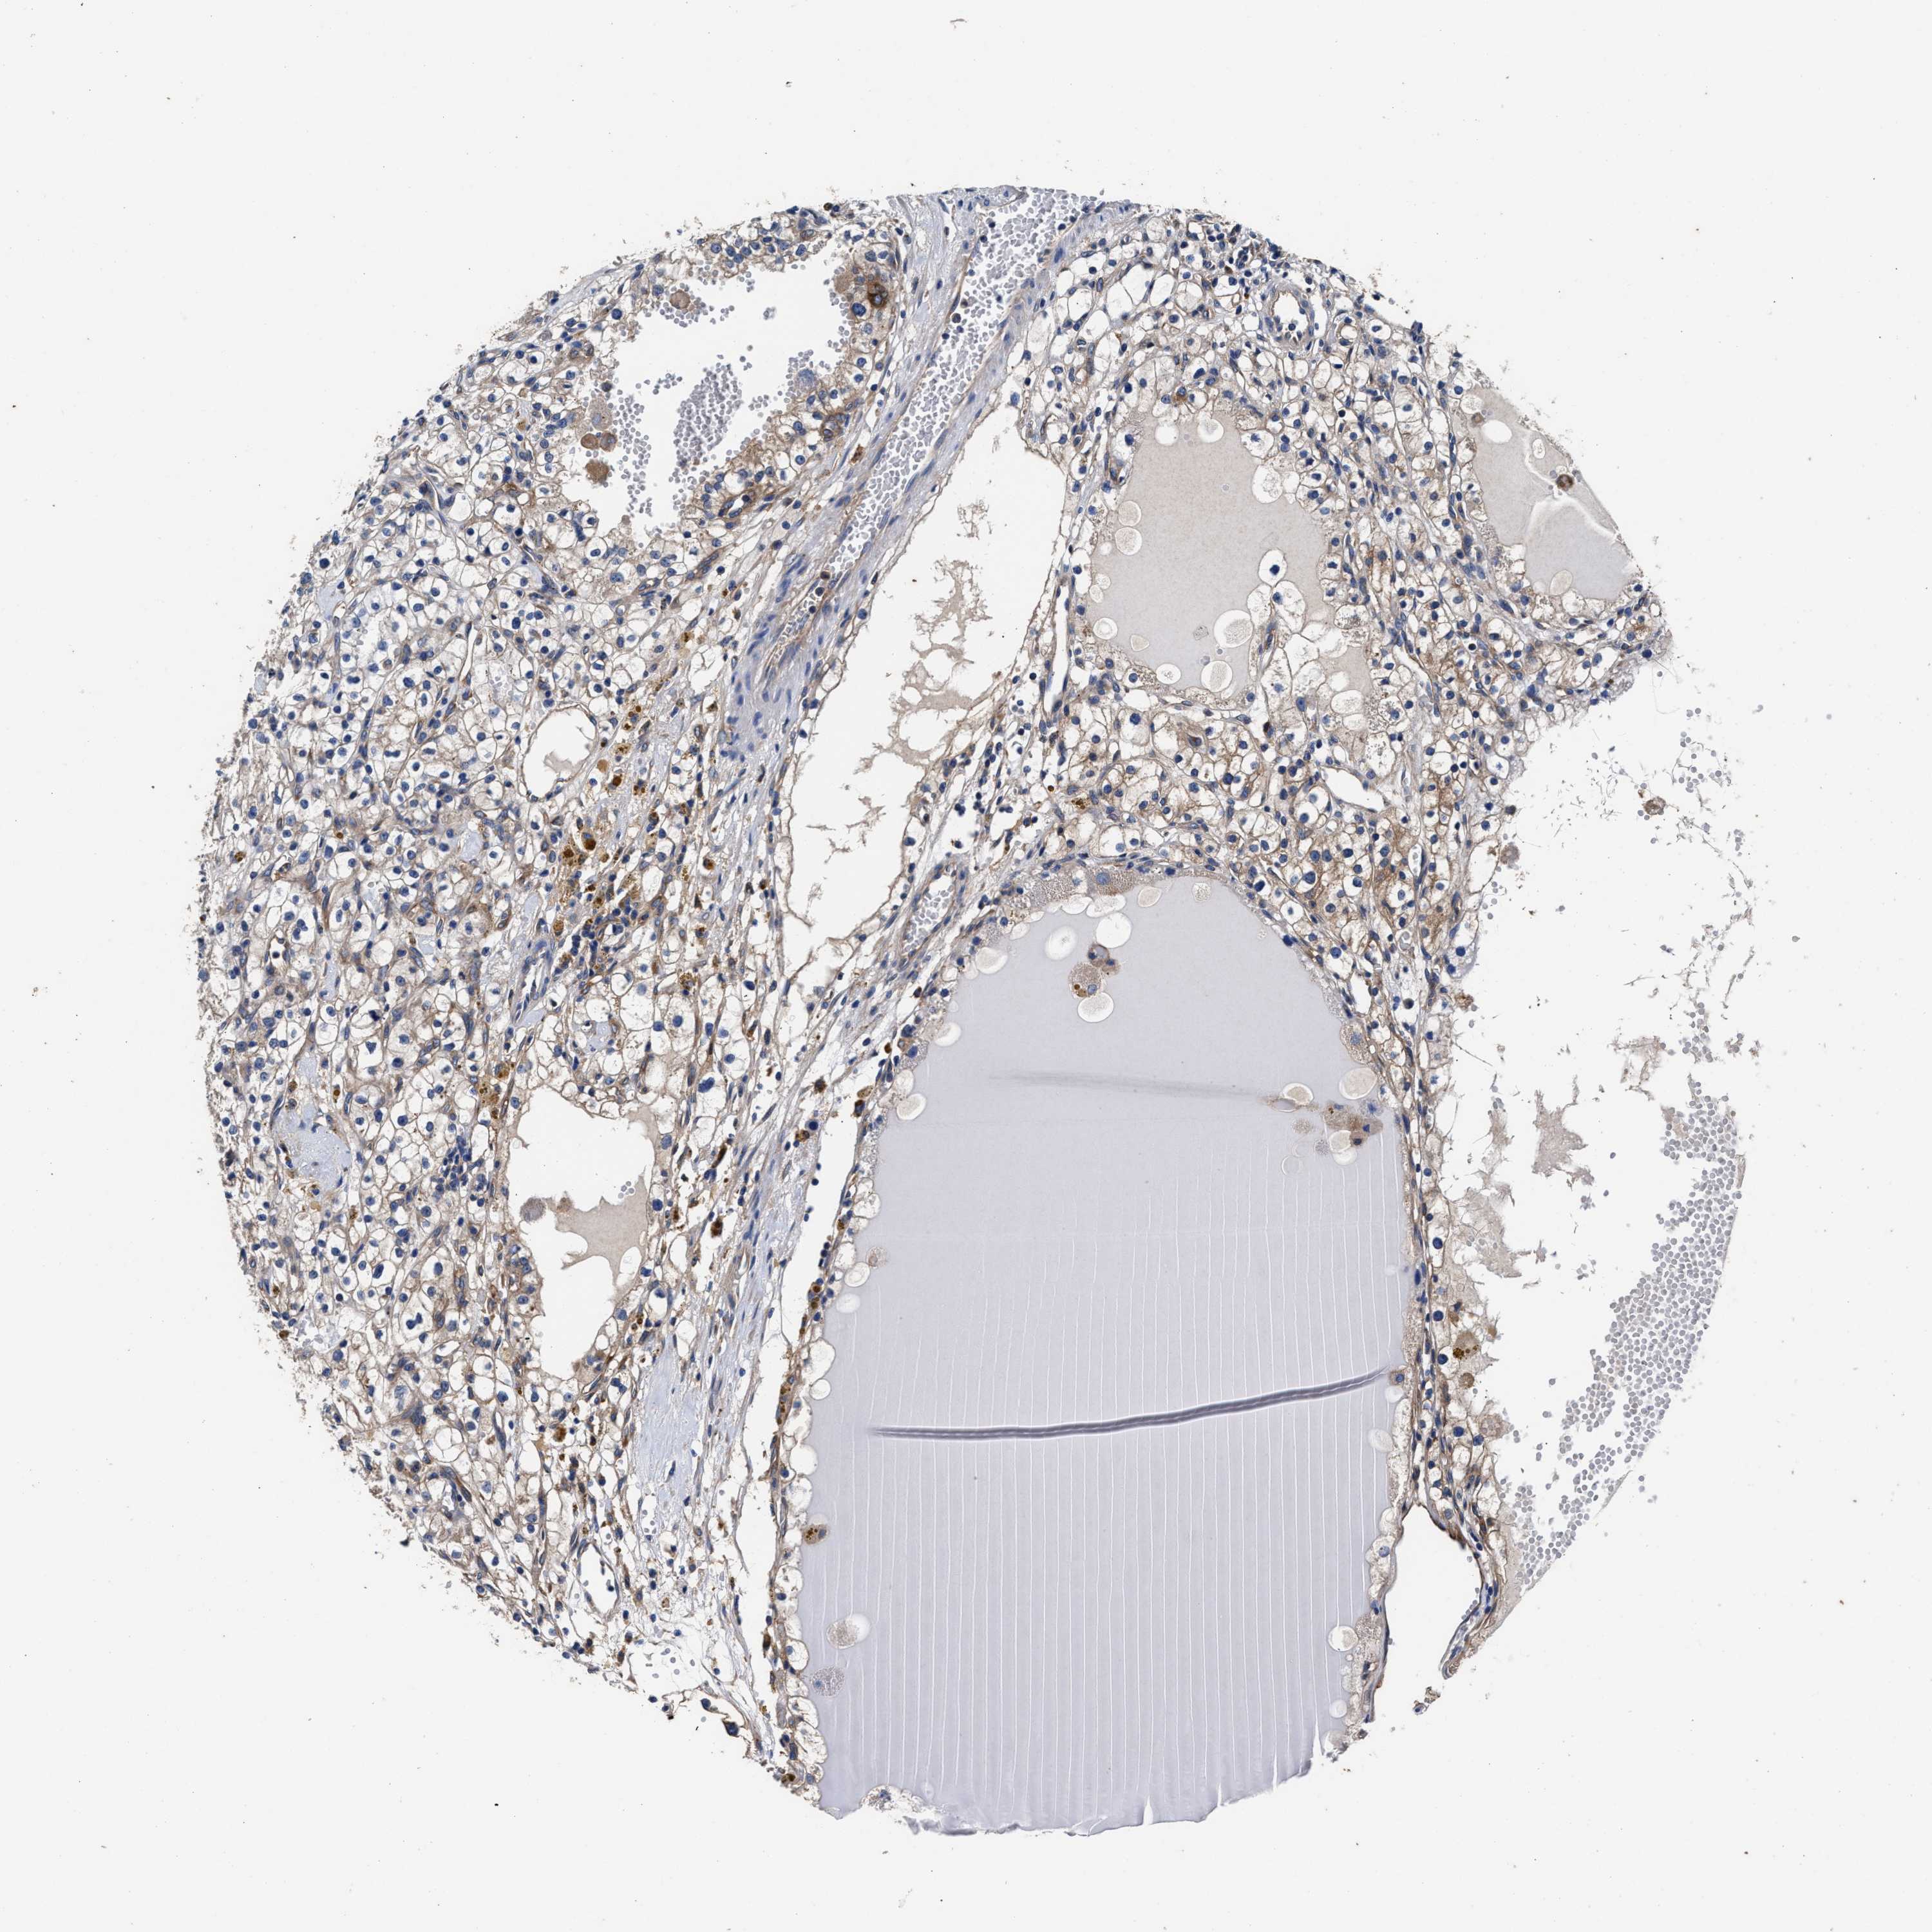

CANCER RENAL CANCER Show tissue menu

KICH TCGA KIRC TCGA KIRC VALIDATION KIRP TCGA PROTEIN RCC CPTAC PROTEIN EXPRESSION